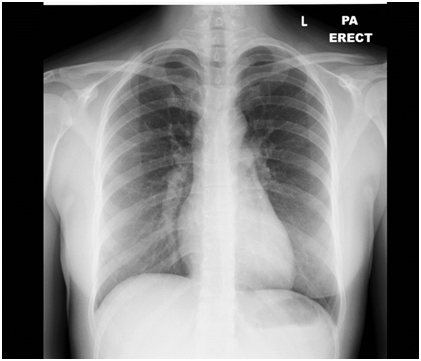

A 23 year old woman previously well presented with a sudden onset severe chest pain and shortness of breath. She was on oral contraceptive pills and has a family history of Protein C deficiency. Her father had recurrent pulmonary embolism from the age of 32 and her grandmother had a history of recurrent strokes from the age of 30. On examination, she was tachycardic, tachypneic and hypoxic. Her CXR was normal (Figure 1). However her CT pulmonary angiograghy showed a saddle pulmonary embolus (Figure 2). She was anticoagulated and booked for an echocardiogram.

Figure 1 Normal CXR.